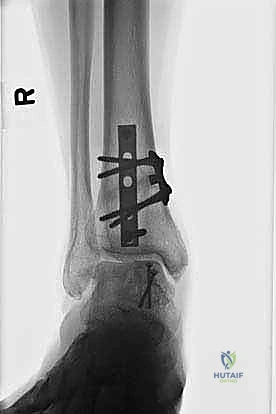

- التصوير بالأشعة السينية (X-rays): الخطوة الأولى لاستبعاد الكسور الكبيرة وتقييم المحاذاة العامة للعظام. قد تظهر الأشعة السينية الآفات الكبيرة، لكنها غالباً ما تفشل في إظهار التلف الغضروفي المبكر.

- التصوير المقطعي المحوسب (CT Scan): ضروري جداً للآفات الكبيرة. يوفر الـ CT صورة ثلاثية الأبعاد للعظم، مما يساعد الجراح في التخطيط الدقيق لعملية قطع العظم وحجم الطعم المطلوب زراعته.